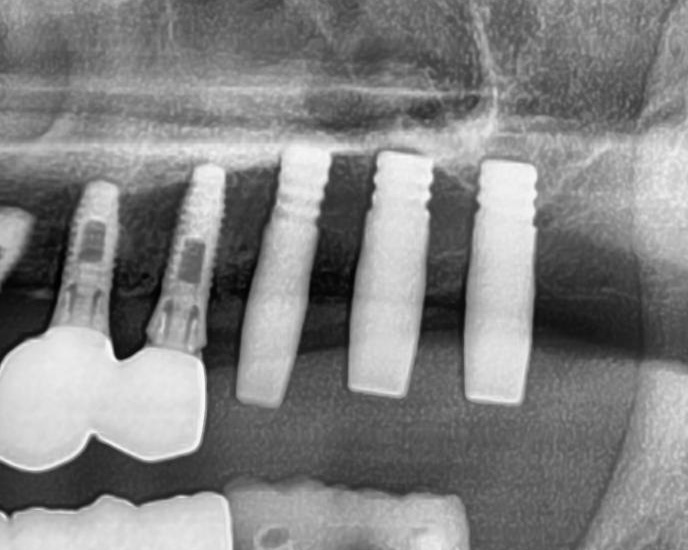

開けた穴に、専用道具を使ってネジを締めるように長さ2センチ程のインプラントを骨に埋め込んでいきます。

続けて他の歯も同じように植立していきます。

インプラントオペでは、複数本を植立する場合でも、当時進行はせず、1本ずつ同じ工程を繰り返して植立します。

しっかりとインプラント埋め込まれた後は、動揺がないか、噛んだ時に当たらないかなどを確認して、最後にパノラマ写真を撮影して今回のオペは終了となりました。